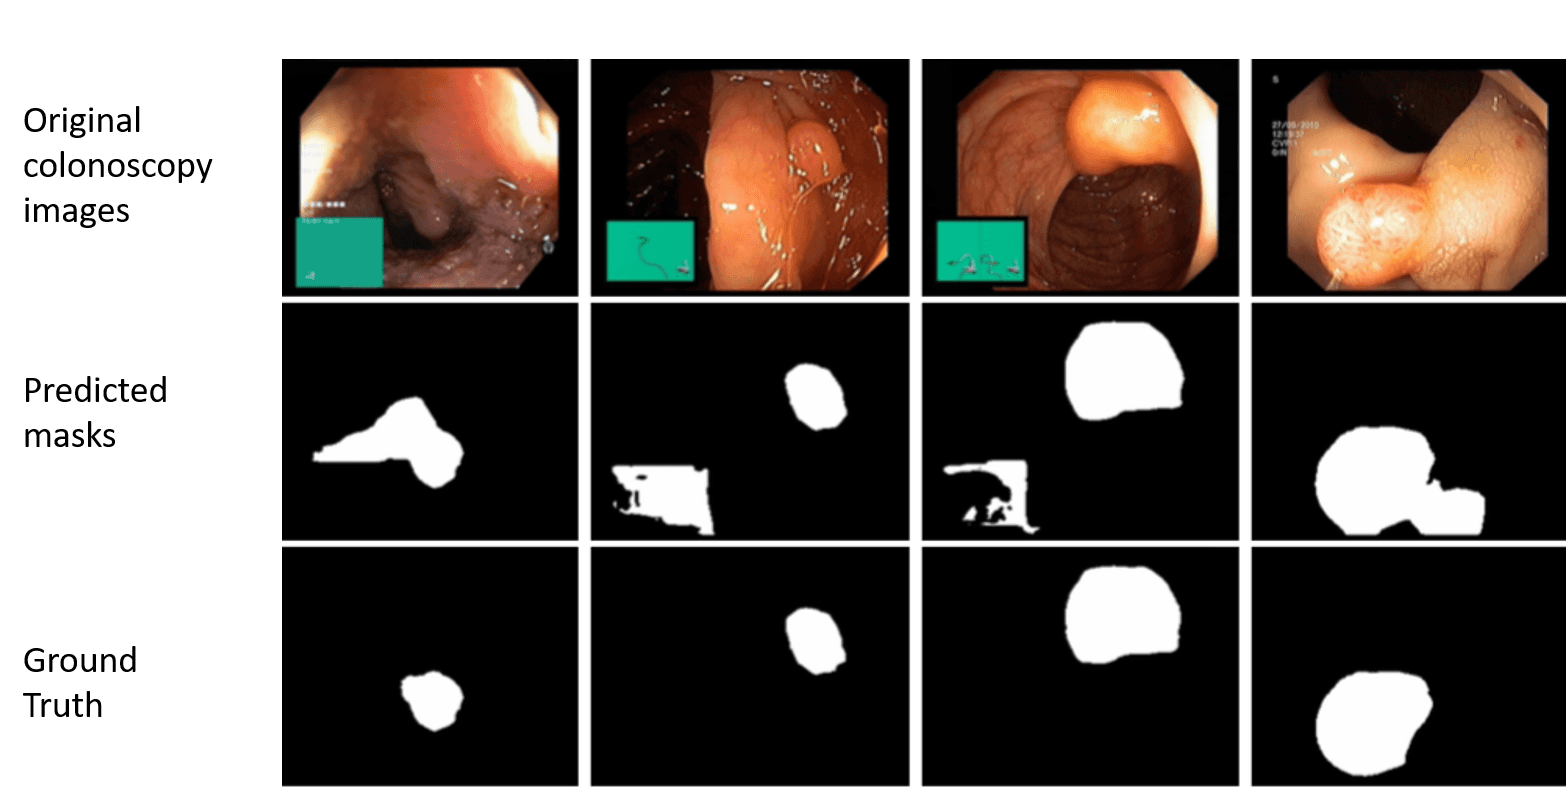

GI Tract Anomaly Detection from Endoscopy Images

Medical Image Analysis | Computer Vision | Deep Learning | Clinical Decision SupportDSDBDB